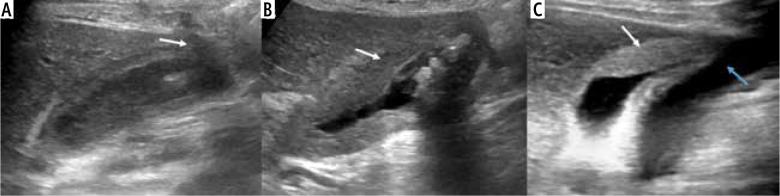

Imaging patterns of wall thickening type of gallbladder cancer.

Gallbladder cancer (GBC) has a high incidence in certain geographical regions. Morphologically, GBC presents as a mass replacing the gallbladder, a polypoidal lesion, or wall thickening. The incidence of preoperative diagnosis of wall thickening type of GBC is less well studied. The patterns of mural involvement and extramural spread are not well described in the literature. Additionally, wall thickening in the gallbladder does not always indicate malignancy and can be secondary to inflammatory or benign gallbladder diseases and extracholecystic causes and systemic pathologies. Objective reporting of gallbladder wall thickening will help us appreciate GBC's early features. In this review, we illustrate the imaging patterns of wall thickening type of GBC.